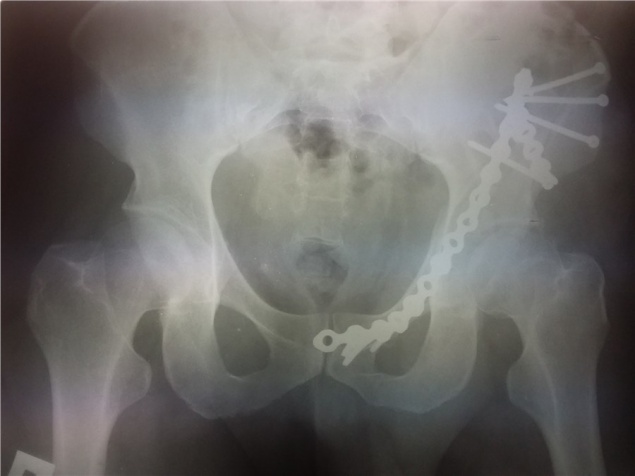

На примере пациента, поступившего в больницу перед самым Новым годом, врачи решили показать, как выглядит тяжелый перелом таза.

«Вертлужная впадина фактически развалилась на части от удара; так как раздроблена большая губчатая кость плюс ко всему большая кровопотеря. Операция длилась три часа, был проведен остеосинтез, сопоставлены отломки. По прогнозам врачей пациент будет ходить, но последствия травмы останутся навсегда», — рассказали в пресс-службе больницы.